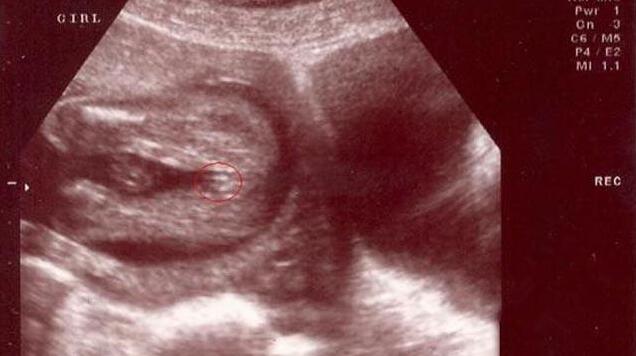

女宝B超图的特征是“三条白线”,当然最好的角度还是从下方来看。如果没有看到三条白线,那么就瞪大眼睛看双腿之间突出的部分,如果特征为两边鼓中间凹,那就基本是女宝了。如下图所示。

三条白线